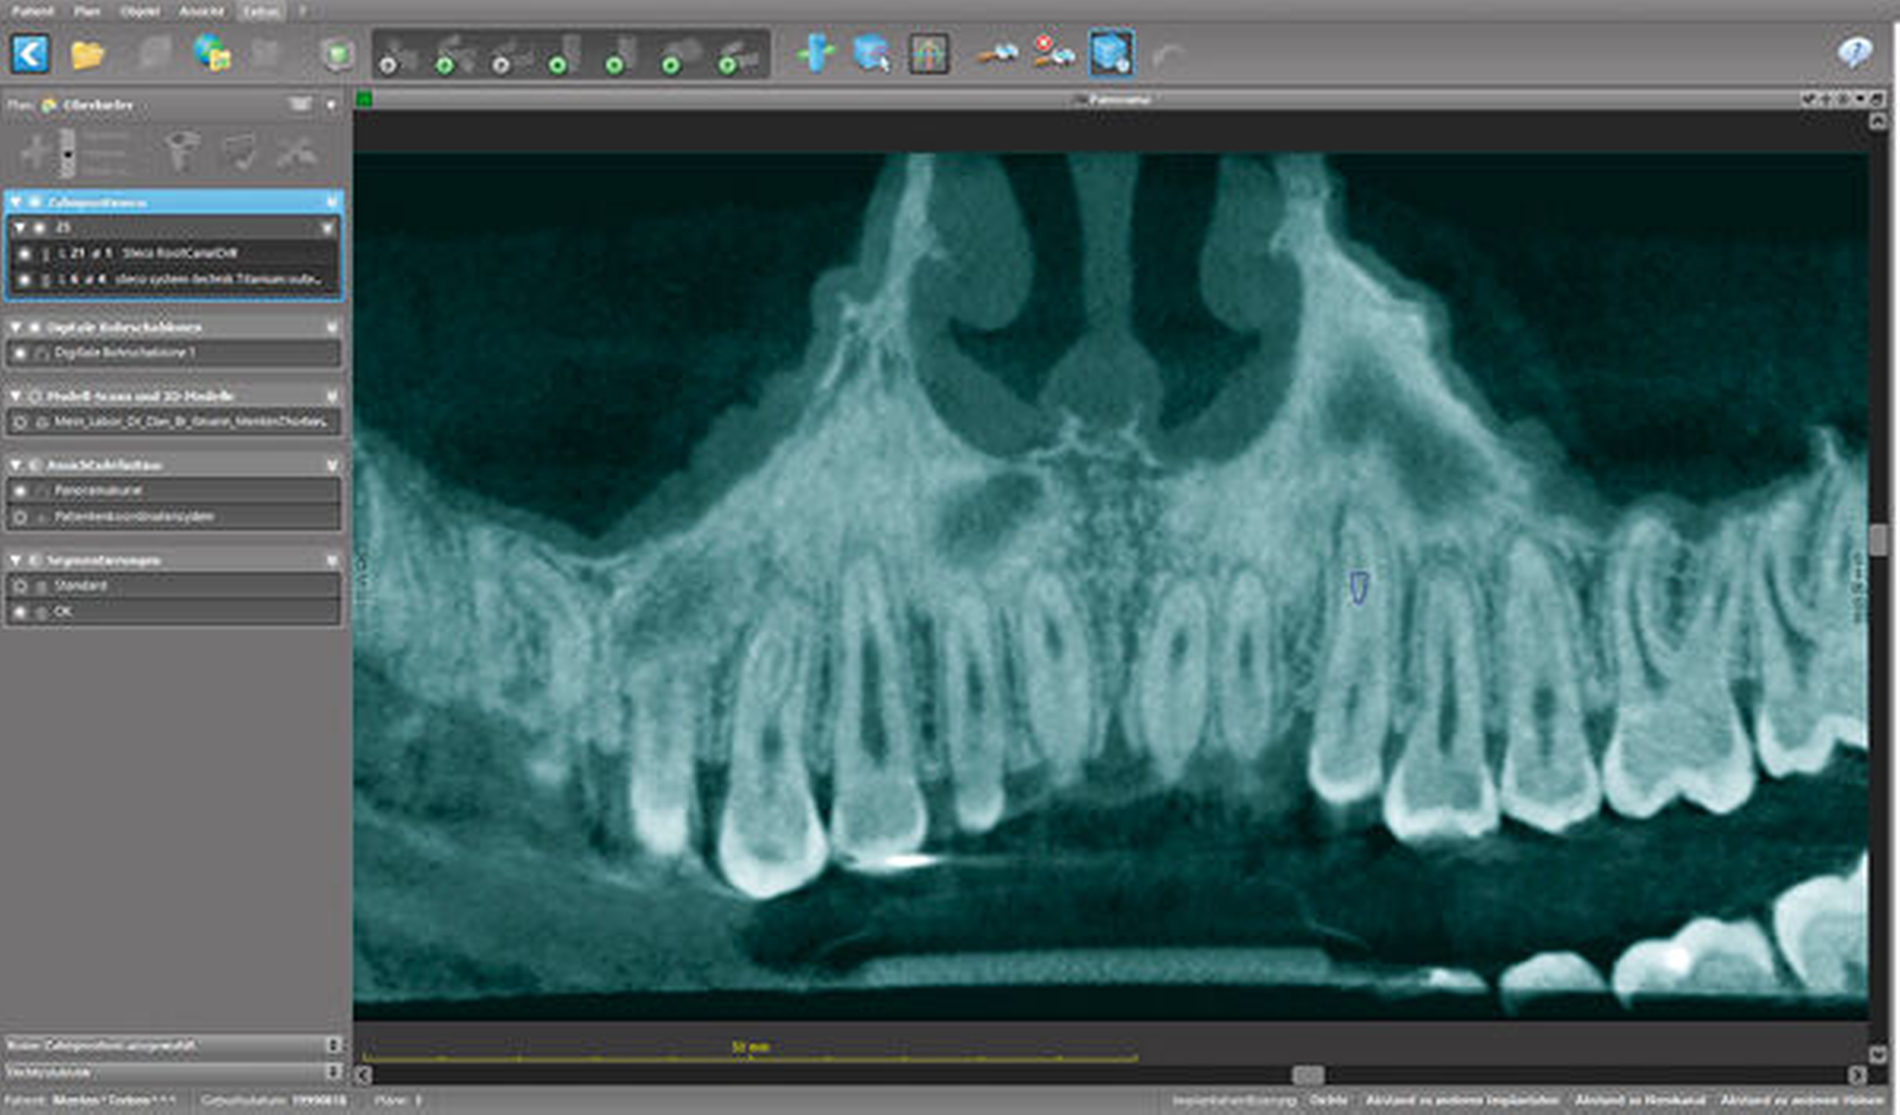

Zunächst wurde hierfür eine DVT–Aufnahme mit einem FOV von 8 cm x 8 cm angefertigt (Orthophos XG 3D, Sirona, Bensheim) und das Oberkiefer-Modell des Patienten gescannt (3Series Dentaler Modellscanner, Dental Wings, Montreal, Kanada). Die DICOM- und SLT-Datensätze wurden anschließend in die Planungssoftware (coDiagnostiX, Dental Wings, Montreal, Kanada) übertragen, fusioniert, und es wurde virtuell eine optimale Zugangskavität geplant. Der verwendete Endoseal-Bohrer (Atec Dental, Ebringen) mit einem Durchmesser von 1,0 mm sowie die auf den Bohrer abgestimmte Endo-Guide-Innenhülse (Steco Systemtechnik, Hamburg) sind in der Software hinterlegt. Bohrer und Hülse werden in der Software so positioniert, dass die Zugangskavität bis in die apikalen Kanalabschnitte erfolgen kann (Abbildungen 5 bis 7). Nach der virtuellen Planung (Abbildung 8) erfolgte die Herstellung der Navigationsschiene mit dem 3-D-Drucker Form 2 (Formlabs, Berlin). Im Anschluss wurde die Hülse in die Schiene eingesetzt (Abbildung 9).